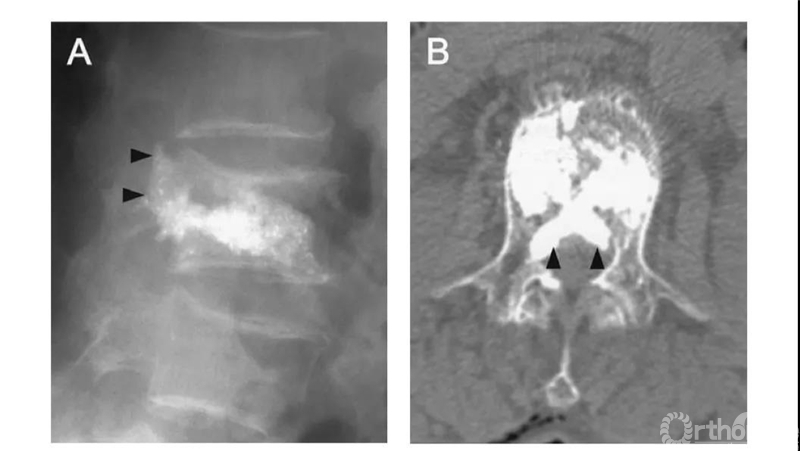

B经椎旁静脉渗漏:在椎体后缘相对对称分布。一般不超过椎管横径的1/3。矢状位CT显示会向头尾侧弥散。

S经节段血管渗漏:沿节段静脉走行弥散。轴位CT呈水平走行。有时会顺着血管上下弥散,矢状面呈垂直或斜行。

比如这例,侧位X片看骨水泥在椎弓根里,可CT一扫发现已经渗漏进入椎管。

侧位X片看骨水泥在椎体里,CT显示渗漏进入椎管。